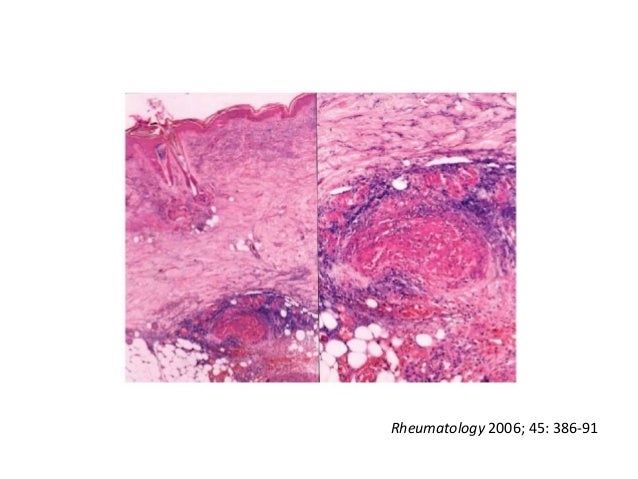

83. 83. 61歳男性• 2年前に対称性多関節炎発症• 関節炎発症前から12kgの体重減少• ESR 100mm/hr以上、CRP 8.5mg/dL• RF 2460 IU/L• Methotrexateによる治療を拒否• Drop footならびにpalpable purpulaが出現→ Rheumatoid vasculitis? Rheumatology 2006; 45: 386-91

84. 84. Rheumatology 2006; 45: 386-91

85. 85. Rheumatology 2006; 45: 386-91

86. 86. 61歳男性• 経口CY + PSLで治療開始 – 当初IVCYだったがコントロールつかず、経口に切り替え• その後、関節症状・血管炎症状とも寛解• 40℃の発熱(quotidian fever)・汎血球減少症で入院• WBC 3000, Hb 5.5, Plt 80K• 骨髄生検: ↑MgK、↑MΦ• 画像検査: 熱源の同定に至らず• 英国NHS → FDG-PET uncovered Rheumatology 2006; 45: 386-91

87. 87. CD2 Cytotoxic Granular PatternCD3 Rheumatology 2006; 45: 386-91